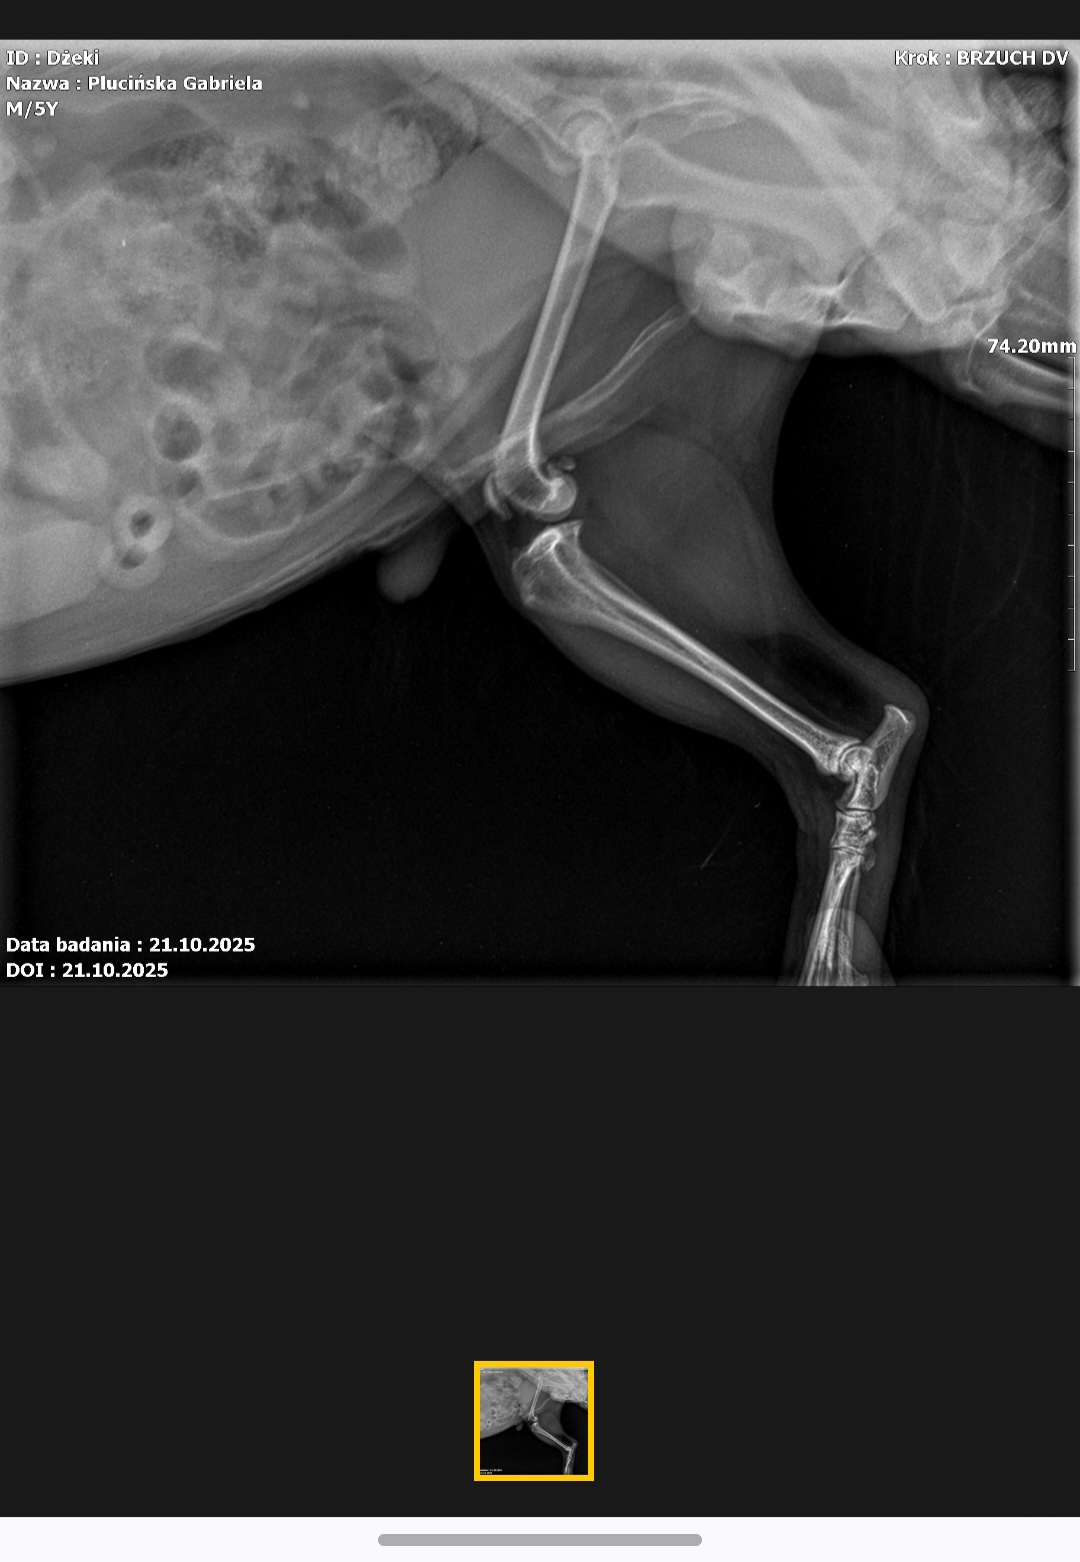

Nasz kochany Jacky to 6-letni yorczek – pełen życia, radości i miłości. Każdy, kto go zna, wie, że to prawdziwy wulkan energii i największy przytulas, jaki istnieje. Zawsze pierwszy przy drzwiach, gotowy na spacer, zawsze obok, gdy komuś w domu smutno. Niestety, ostatnio spotkał go nieszczęśliwy wypadek. Podczas zwykłego, codziennego wskakiwania na łóżko poślizgnął się i zwichnął staw kolanowy. Od tamtej chwili nie może normalnie chodzić – kuleje na prawą łapkę, a każdy krok sprawia mu ból.

Po wykonaniu RTG weterynarz potwierdził, że konieczna jest operacja, której koszt to około 3000 zł, a po niej rehabilitacja i wizyty kontrolne, które są dodatkowo płatne. Niestety, to wszystko przekracza nasze możliwości finansowe, a tak bardzo chcemy, by Jacky znów mógł biegać, skakać i cieszyć się życiem tak jak dawniej.